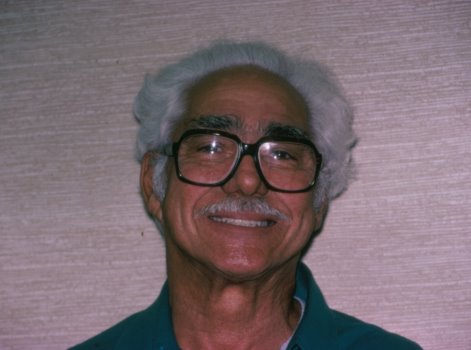

This patient had worn a complete set of dentures for over thirty years.

Because of this, he was no longer able to wear a lower denture due to a

normal atrophy, or withering away, of his lower gum ridge. We placed four endosseous implants into his jawbone and allowed bone to form

around them for six months. Then, a set of lower teeth was constructed

and was fastened to the implants with screws. This patient’s original

request was to be able to eat peanuts, something that most of us with

teeth take for granted. Now, this happy fellow can eat all of the

peanuts that his heart desires. |